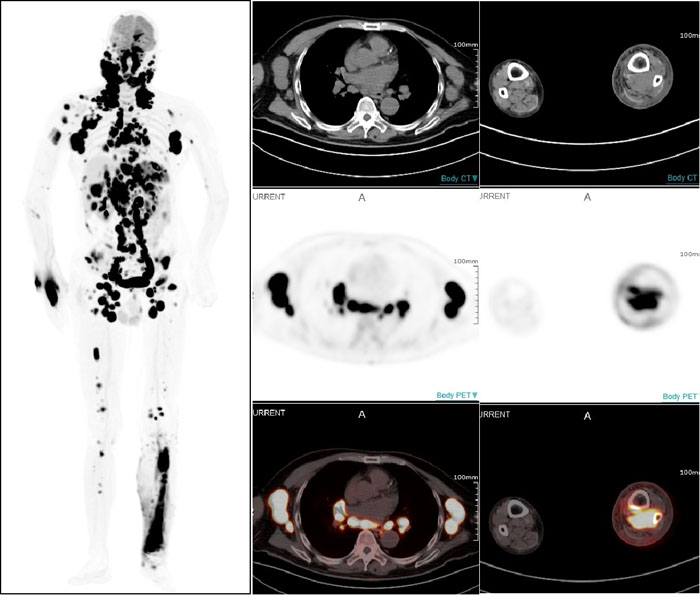

PET/CT顯示:全身多部位淋巴結和多個結外器官及不易發現的左小腿后方肌肉組織淋巴瘤受累病灶

一名67歲男性患者因近期無明顯誘因出現左頸部淋巴結腫大而就醫,淋巴結切檢病理診斷為非霍奇金彌漫大B細胞淋巴瘤。借助全景動態Total-body PET/CT掃描,不僅確認了此前的診斷,還發現腫瘤已廣泛累及全身多處淋巴結及乳腺、胸膜、肝臟、脾臟、胃等多個結外器官。更令人稱奇的是,連平時難以察覺的右小腿深部肌肉組織病變也被準確捕捉。這一全面而精確的影像信息,有效提升了治療的針對性,為醫生制定個性化治療方案奠定了堅實基礎。

設備全身動態采集的性能,清晰展現出藥物在體內的流動、擴散及被組織器官攝取并代謝的全過程,幫助醫務人員觀察藥代動力學改變,可以預見,將為腫瘤診療、新藥研究、細胞追蹤等領域帶來更多革命性突破?。